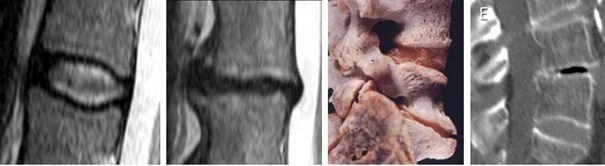

- Magnetic resonance imaging (MRI) based on which mainly the bony involvement of the spine, and any significant narrowing of the spinal canal are ruled out, which may be contraindications.

- Computerized tomography (CT) based on which the operable intervertebral disc spaces are eventually identified, and the surgery could be planned.

The empty and flat intervertebral disc spaces are filled up through the skin (percutaneously) from a tube with a diameter of about 5 mm, which ends in a cone. A device is inserted into the area of all intervertebral disc spaces (from the right or the left side depending on the direction from where the asymmetrical degenerated space should be corrected). During the initiation of the operating channel and the duration of the whole surgery, the precision of the working process is controlled from two directions by using an X ray image intensifier.

A semifluid, viscous filling material (bone cement or PMMA i.e., poly methyl methacrylate) is injected into the prepared intervertebral disc space. The material fills out the empty space, which is bordered by the bony endplates from the direction of the head and the legs, and the degenerated and thinned intervertebral disc wall centrally. We wait until the cement hardens (10 14 minutes), then the injecting device is removed. Usually, the wound, which is only a few millimeters big, is not stitched up, only glued.

This procedure may be repeated by every one or two intervertebral discs, until the intervertebral discs which are marked for surgery are treated. A bidirectional follow-up X ray scan is performed at the end of the surgery.